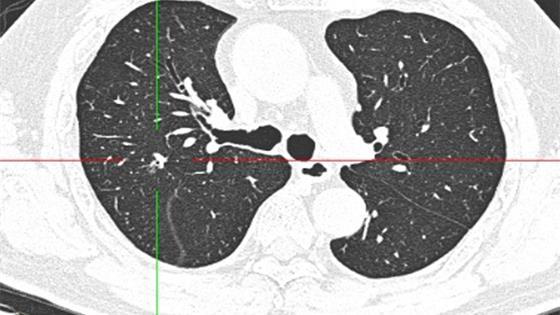

孤立性肺结节是指单一的、边界清楚的、影像不透明的、直径小于或等于30毫米、周围为含气肺组织所包绕的病变,没有肺不张、肺门增大或胸腔积液表现的肺部结节。 详细»

高天 高天 副主任医师 西京医院

患者在入院13天前,经常出现咳嗽、发热无力等症状,一开始以为只是普通的疾病没有给予重视,于是病情严重后,持续一个月余,才意识到疾病的严重性,于是来到我院进行救治,经过胸部CT的检查,发现患者右肺上叶后段近斜裂胸膜见1个实... 详细»

肺结节呈独立性,它的边界清楚、直径不超过30毫米,含气的肺组织包绕患处周围,是没有肺不张、肺门增大或胸腔积液表现的肺部结节。 详细»